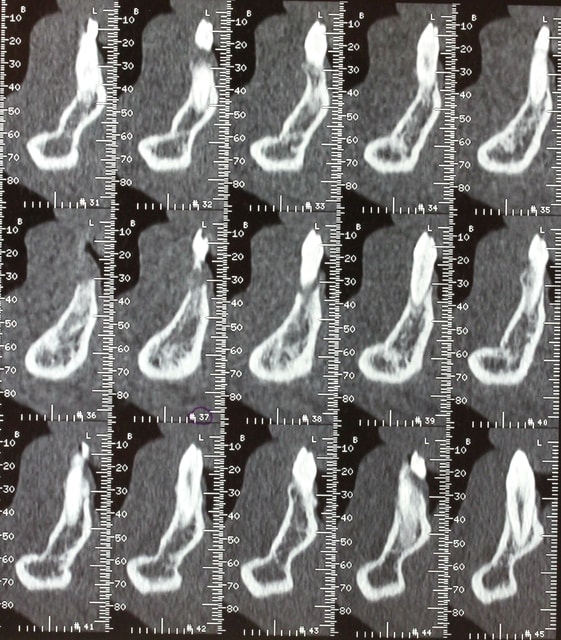

Voici le dentascan de la mandibule que je viens d ostéotenser ce jour. Deuxième séance ds 45 j et puis 45 plus tard implants en enfouis probablement

Zones molaires creuses et zones des PM denses car deux tori mandibulaires sont présent

Dès que les implants y seront vous le saurez mais vu la forme assez bizarre de la mandibule en zone molaire il y aura d abord un modèle Materialise avant la chirurgie, histoire de voir si les plaques sont indispensables ou si les disks pourront passer ds ce relief assez "courbe"

Pp ;-)